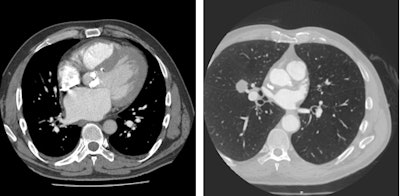

A case in point, van Beek remembers a CT scan that showed a right coronary artery anomaly (shown in figure below). He insisted on a reconstructed full field-of-view and discovered metastatic breast cancer, which changed management of the patient to extensive chemotherapy before coronary surgery. This also led to a shift in the cardiologist's mind at the time as to the usefulness of reconstructed full field-of-view images.

Patient presenting with suspected anomalous right coronary artery. Coronary CT angiography shows interarterial right coronary artery (left, also shown on 3D reconstruction in center). Full field-of-view reconstruction reveals spiculated lung lesion, which proved to be metastatic breast cancer (right). Images courtesy of Dr. Edwin van Beek, PhD.ECR 2016 delegates will also be reminded of the subtle information available on CT and MR such as abnormal shape (D-shaping) of the interventricular septum, which may indicate pulmonary pressure overload or how thickened interlobular septae and pulmonary ground-glass opacities on CT may point to pulmonary congestion secondary to heart failure.